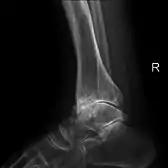

Diagnosis is made with reasonable certainty based on history and clinical examination.[51][52] X-rays may confirm the diagnosis. The typical changes seen on X-ray include: joint space narrowing, subchondral sclerosis (increased bone formation around the joint), subchondral cyst formation, and osteophytes.[53] Plain films may not correlate with the findings on physical examination or with the degree of pain.[54]

- Primary osteoarthritis of the left knee. Note the osteophytes, narrowing of the joint space (arrow), and increased subchondral bone density (arrow).